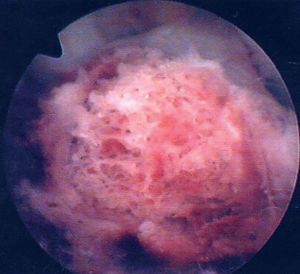

* Dificultad en la visión por la grasa de Hoffa, por la hemorragia o por el ligamento transverso: primero una irrigación generosa, después resección parcial de la grasa de Hoffa, después rechazo del ligamento transverso y reducción del fragmento por debajo del ligamento transverso (figs. 15a y b).

Figuras 15a y b

Esquema (a) y foto artroscópica del ligamento transverso (b).